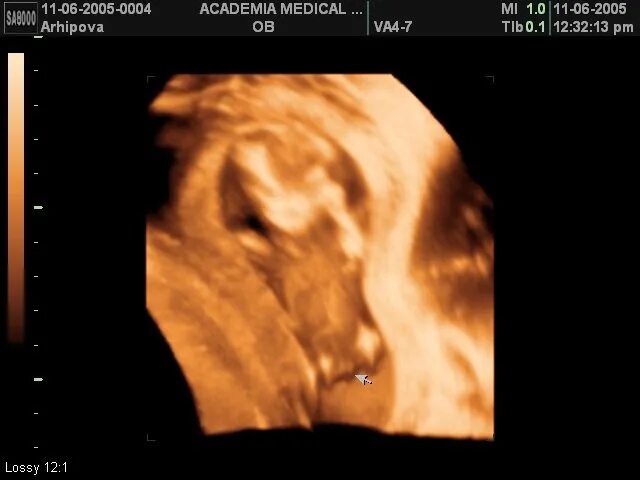

Могут ли ошибаться узисты с полом